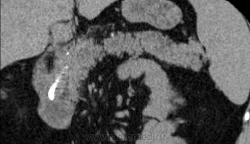

Итак пациент мужчина 34 года, в анамнезе - 16 эпизодов острого панкреатита (!). Пациенту была выполнена ЭРХПГ которая выявила наличие двух стриктур протока Вирсунга в области головки поджелудочной железы (доброкачественная стриктура Вирсунгова протока). На представленных мной изображениях определяется неоднородная структура поджелудочной железы с гиподенсными участками в области тела/хвоста и наличием паренхиматозных кальцификатов (b & c). Такая картина указывает на хронический панкреатит. В области головки визуализируется стент (a), установленный в Вирсунгов проток, с свободным концом в просвете 12-ти перстной кишки. Такое стояние стента является правильным. На данный момент, единственной адекватной терапией при доброкачественных стриктурах протока поджелудочной железы (и при некоторых опухолях исходящим из протока или обтурирующих его, когда невозможно выполнить резекцию) является эндоскопическое стентирование протока, что обеспечивает нормальный отток секрета поджелудочной в кишечник.